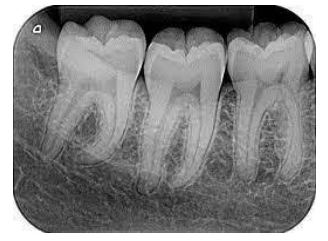

Diante disso, analise a radiografia a seguir:

Essa é uma radiografia do tipo: